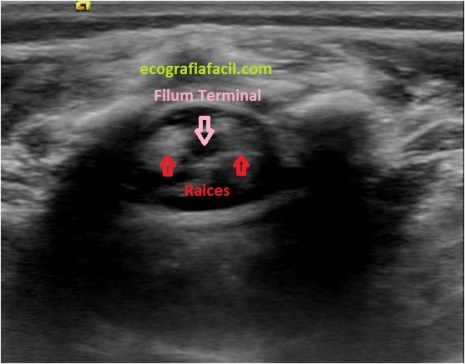

Debemos ver y comprobar que el Filum Terminal no esté engrosado, para esto necesitamos un corte axial.

We must see and verify that the Terminal Filum is not thickened, for this we need an axial cut.

Comprobaremos normalidad de raíces nerviosas, y saco tecal.

We will check normality of nerve roots, and thecal sac.